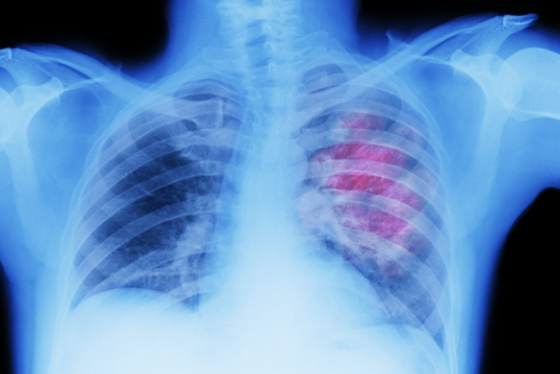

폐암은 병기(staging)에 따라 1기부터 4기로 나뉩니다. 그중 4기는 암세포가 폐뿐 아니라 다른 장기까지 퍼진 상태로, '전이'가 있는 말기 폐암을 의미합니다. 림프절, 간, 뼈, 뇌 등으로 전이가 발견되면 4기로 진단됩니다.

이 단계에서는 수술적 치료보다는 전신 치료가 중심이 되며, 항암요법이나 면역치료, 표적치료 등 다양한 접근이 이뤄집니다. 하지만 모든 환자가 같은 상태는 아니며, 폐암 4기 중에서도 전이된 위치와 범위, 환자의 상태에 따라 차이가 큽니다.